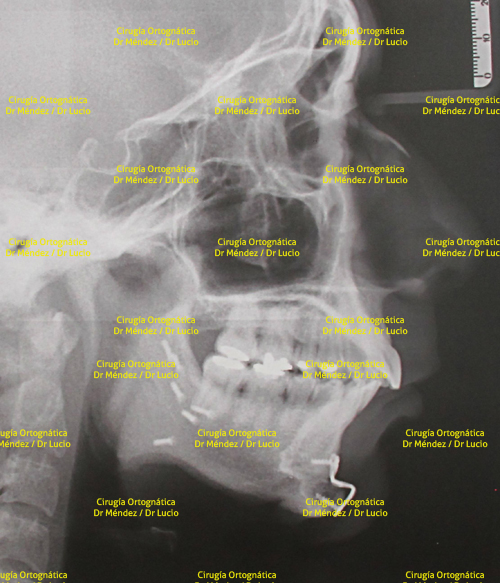

RETROGNASIA E HIPOPLASIA DEL MENTÓN Paciente operado de avance de mandíbula y mentoplastia de avance |

||

![]() |

|